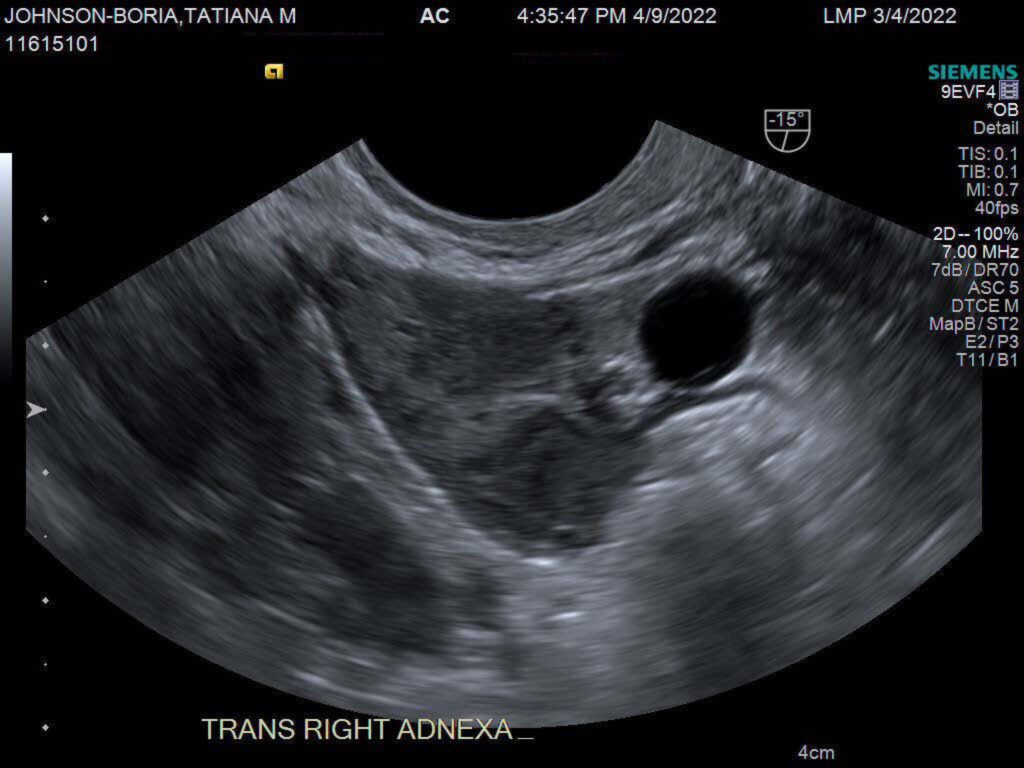

About a week after finding out my partner and I were pregnant, we learned the pregnancy was no longer viable. We’d been planning for this pregnancy, so it was not only a devastating moment, but it was also a moment that forced me to understand that I am not as in control of my body as I like to believe. I’ve become well-versed in believing I have control. Growing up with my mother’s mercurial shifts fostered a strong yearning for stability within me. I became good at finding my own sense of control even when the universe of my childhood couldn’t provide it. I willed myself to survive the chaos of my childhood and because I survived, I believed that I could not only control the trajectory of my life, but my mind and my body.

When I shared my partner and I’s experience with pregnancy loss to some Black women in my life, they all had experienced similar losses. Before I left the hospital, after learning about my declining HCG levels, a Black nurse told me about her four miscarriages. The number of Black women experiencing pregnancy loss is immense. The more I hear other stories, the more I can’t stop thinking about our individual and collective strength, yet what I never think about is our rest.